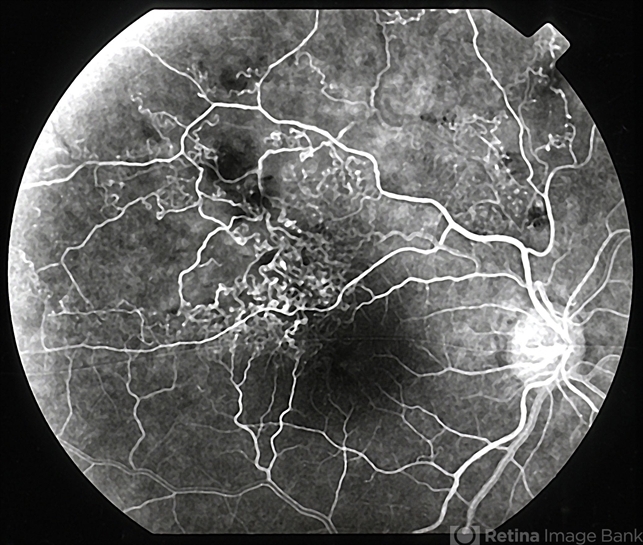

- Retinal vein occlusion

- branch retinal vein occlusion (BRVO)

- Delayed-onset visual loss due to leakage from telangiectatic vessels in an eye with previous branch retinal vein obstruction (BRVO). Fluorescein angiogram 2 of 4.